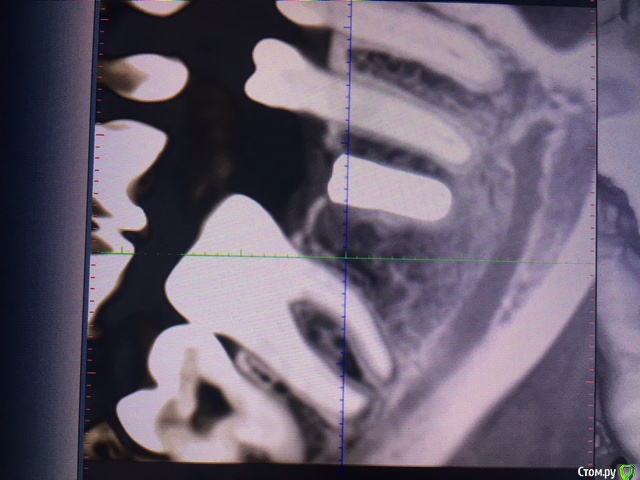

evaverkina Опубликовано 22 февраля, 2018 Автор Поделиться Опубликовано 22 февраля, 2018 (изменено) Фото КТ Изменено 22 февраля, 2018 пользователем evaverkina Ссылка на комментарий

evaverkina Опубликовано 22 февраля, 2018 Автор Поделиться Опубликовано 22 февраля, 2018 Сделайте Кт Фото КТ прикрепила, есть возможность отправить вам КТ целиком или этого достаточно? Ссылка на комментарий

red_butler Опубликовано 22 февраля, 2018 Поделиться Опубликовано 22 февраля, 2018 Зуб не травмирован Ссылка на комментарий

Bier Опубликовано 23 февраля, 2018 Поделиться Опубликовано 23 февраля, 2018 По КТ все хорошо. Ссылка на комментарий